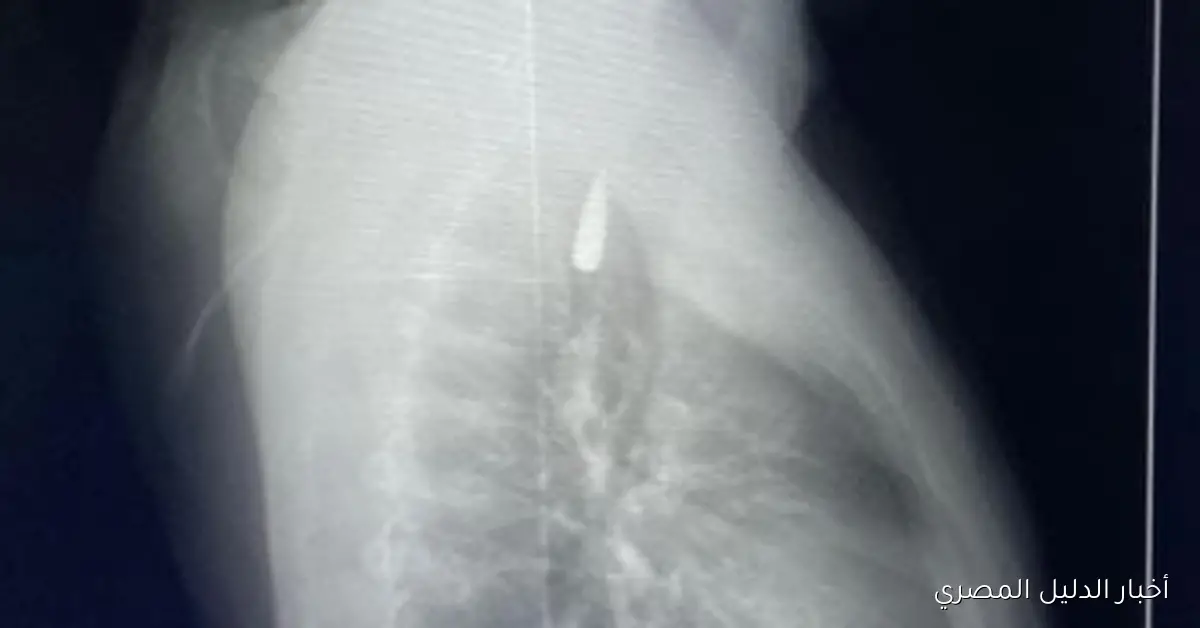

من جهته، أوضح الدكتور تامر عبد الله، عميد كلية الطب ورئيس مجلس إدارة المستشفيات الجامعية، أنه في يوم 21 أكتوبر 2025، تمكن فريق من أطباء قسم جراحة القلب والصدر والتخدير والمعاونين من إجراء جراحة دقيقة بالغة الخطورة لأحد المرضى المحجوزين من قطاع غزة، الذي تعرض لإصابة بطلق ناري في الرأس، استقر المقذوف على إثرها داخل تجويف القفص الصدري قرب الشريان الأورطي، وهو الشريان الأكبر والأهم في الجسم المسؤول عن تغذية جميع الأعضاء الحيوية، وأضاف أن الفريق الطبي، على الرغم من دقة الحالة وتعقيدها، نجح في استخراج المقذوف بأمان بعد عملية جراحية نادرة استمرت عدة ساعات داخل المستشفى الجامعي الجديد، حيث خضع المريض بعدها للرعاية الطبية اللازمة وحالته الآن مستقرة وتحت المتابعة الدقيقة من الفريق المختص.